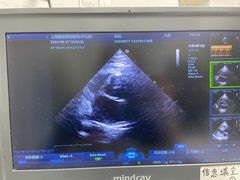

• 爱侣宠医·鹦鹉专科·小型哺乳类·异宠专科(灵石路店)

• -爱侣宠医·鹦鹉专科·小型哺乳类·异宠专科(灵石路店)